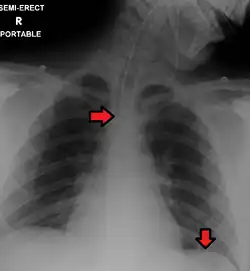

In anteroposterior (AP) views, the positions of the x-ray source and detector are reversed: the x-ray beam enters through the anterior aspect and exits through the posterior aspect of the chest. AP chest x-rays are harder to read than PA x-rays and are therefore generally reserved for situations where it is difficult for the patient to get an ordinary chest x-ray, such as when the patient is bedridden. In this situation, mobile X-ray equipment is used to obtain a lying down chest x-ray (known as a "supine film"). As a result, most supine films are also AP.

Typical views

Required projections can vary by country and hospital, although an erect posteroanterior (PA) projection is typically the first preference. If this is not possible, then an anteroposterior view will be taken. Further imaging depends on local protocols which is dependent on the hospital protocols, the availability of other imaging modalities and the preference of the image interpreter. In the UK, the standard chest radiography protocol is to take an erect posteroanterior view only and a lateral one only on request by a radiologist.[5] In the US, chest radiography includes a PA and Lateral with the patient standing or sitting up. Special projections include an AP in cases where the image needs to be obtained stat (immediately) and with a portable device, particularly when a patient cannot be safely positioned upright. Lateral decubitus may be used for visualization of air-fluid levels if an upright image cannot be obtained. Anteroposterior (AP) Axial Lordotic projects the clavicles above the lung fields, allowing better visualization of the apices (which is extremely useful when looking for evidence of primary tuberculosis).